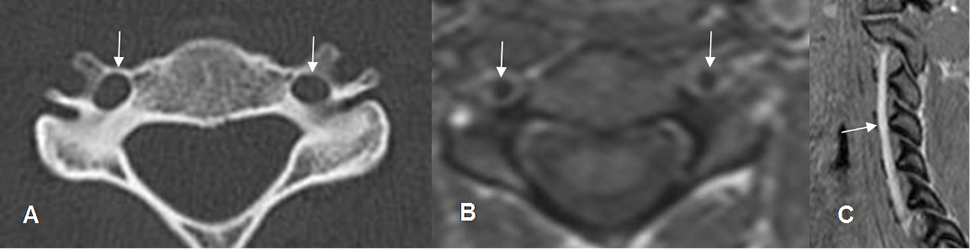

Fig 210. Vertebral normal.

A: TAC axial. Forámenes vertebrales, en las apófisis transversas cervicales.

B: RM axial en T1. Arterias vertebrales normales, con ausencia de señal.

C: RM sagital en GE. Arterias vertebrales hiperintensas, de aspecto normal.